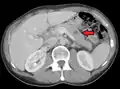

Pulmonary metastases shown on Chest X-Ray